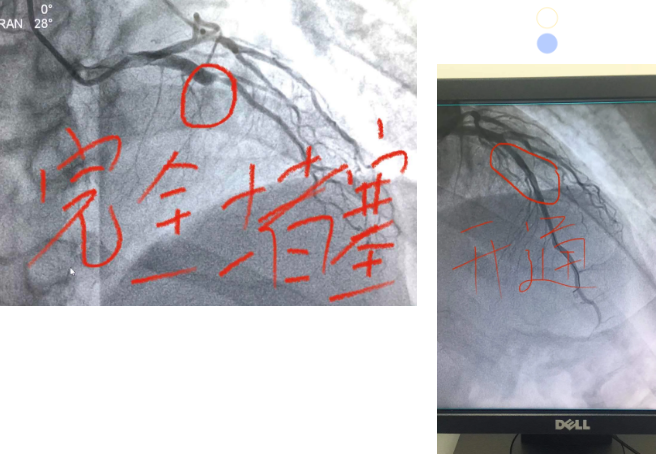

接诊三例急性心梗

幸得心内科、介入诊疗室医护紧急实施介入手术

均成功开通血管

成功挽救心肌